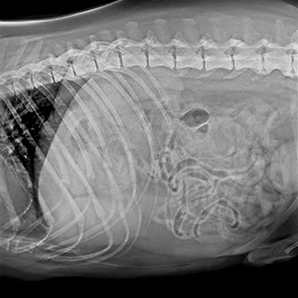

L'imagerie à faible dose est conviviale pour les animaux de compagnie tout en acquérant des images haute résolution pour le diagnostic.